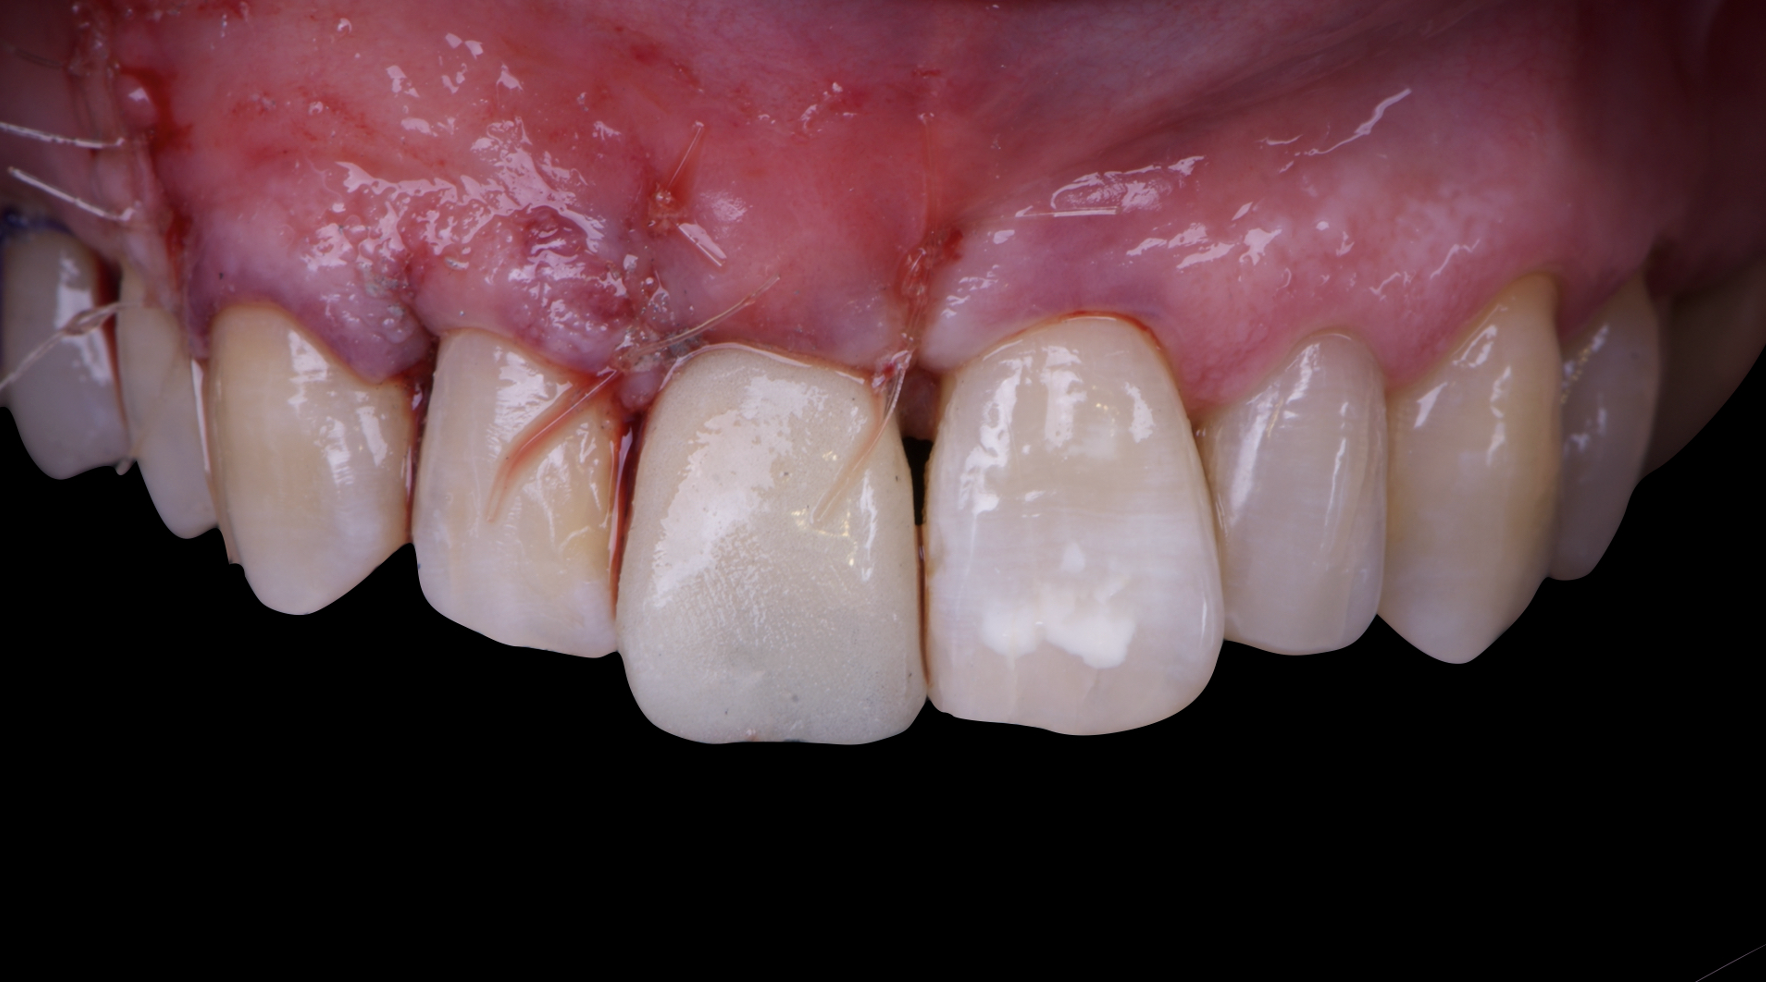

Given the significant buccal defect, guided bone regeneration (GBR) was performed simultaneously. A mixture of autologous bone and creos™ xenogain™ was applied to the defect and covered with a resorbable creos™ membrane to restore ridge width and support the buccal contour. In addition, a connective tissue graft was harvested and placed in the vestibular region to increase the thickness of keratinized mucosa. This combined approach addressed both hard and soft tissue deficiencies, providing the biological foundation for a stable and esthetic outcome.

On the same day as the surgery, an immediate-load provisional crown was delivered. This restoration was fabricated in acrylic resin and screw-retained on the implant, following the “one abutment one time” principle. The provisional crown was carefully adjusted to avoid occlusal loading while supporting the peri-implant soft tissue architecture during the healing phase.

The provisional not only satisfied the patient’s functional and esthetic demands but also played a key role in shaping the emergence profile and conditioning the gingival margin. By providing a provisional solution immediately, the patient was able to leave the clinic with a natural-looking smile, avoiding any psychological or social impact associated with tooth loss in the anterior maxilla.